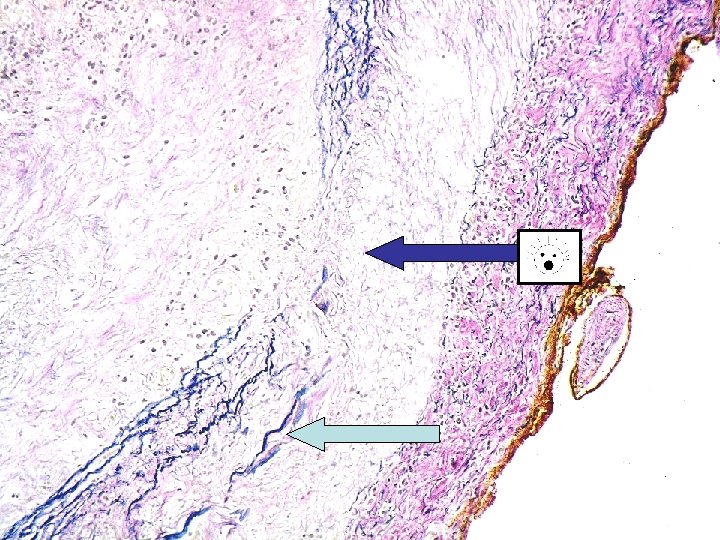

Normal TA intima media adventitia Bluish curly line

intima media adventitia

Bluish curly line is internal elastic lamina

Temporal arteritis Idiopathic, granulomatous vasculitis of large or medium sized elastic arteries. SKIP LESIONS Predilection for superficial temporal artery, but can affect cerebral arteries, carotids, coronary arteries, aorta, renal arteries etc… Pathogenesis-actinically damaged elastic tissue-trigger cell-mediated immune response ? Infection? Histology-with and without giant cells. Adventitial acute and chronic inflammation with involvement of media (muscle layer). Fragmentation of internal elastic lamina. Giant cells at sites of internal elastic lamina rupture (not always). Inflammatory oedema of intima, with stenosis of lumen.